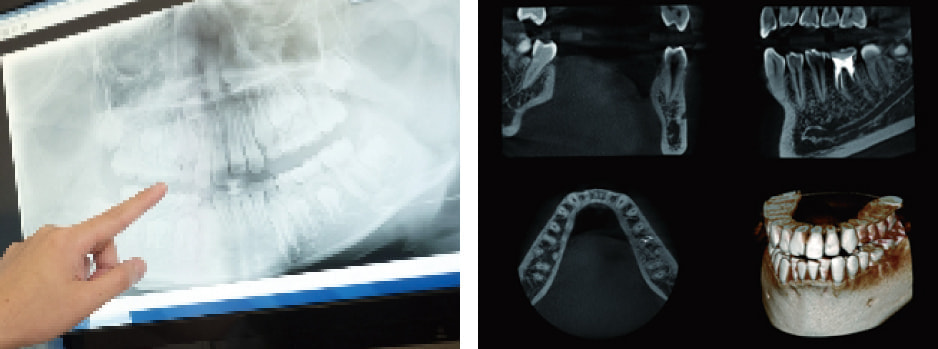

デジタルレントゲン・CT診断装置

すべてのレントゲンを撮る際に、デジタルレントゲンで撮影しております。

デジタルレントゲンのメリットは放射線量(被爆量)が従来のレントゲンの約4分の1におさえる事ができるという点です。

放射線量が少ないですから、妊婦さんや子供でも、安心してレントゲン撮影を受けていただけます。

撮影したレントゲンをモニターで見ることが出来ますし、見たい部分を、大きく拡大することが可能です。

撮影後は各診察台に設置されたモニターのレントゲン映像を見ながら分かり易く説明いたします。

これにより、虫歯の早期発見・治療・予防に効果的です。

CT3次元CT撮影診断装置も導入していますので、より高度な診断を行うことができます。